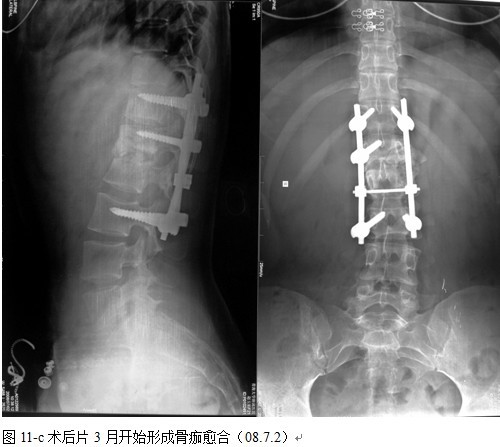

本组手术用时间3~4h , 平均3.5h 。术中出血300~500ml , 平均约350ml 。术后症状完全缓解,无神经功能障碍加重等并发症,1例营养差的老年患者伤口出现窦道,1例因肝功能差,术后未口服抗痨药,伤口出现窦道,经换药后二期愈合,其余病例伤口均一期愈合。马尾神经受损的患者术后基本恢复正常。术后一周后凸角平均 5.4°后凸畸形平均矫正90%以上, 最终后凸角平均8.3°,后凸角度平均丢失4.2°。随访3个月有87%(40/46)有骨痂形成,6个月91.3%(42/46)明显骨性愈合(见图),其余4例9-12个月内愈合,随访时间3-32个月,平均11个月,46例患者中2例在术后2个月和3个月时背部形成脓肿,换药后治愈。2例出院1月后并发结核性脑膜炎,治疗后好转。1例因椎弓根钉偏外,刺激神经根,5个月后从侧方脱出,疼痛加重,因前后路植骨完全愈合,取出后症状完全缓解。

中国学者金大地[22]等采用一期前路病灶清除植骨前路钢板固定治疗腰椎结核,平均18°的后凸畸形得以矫正,Mukhtar[23] AM等采用前路病灶清除植骨分期或同期后路固定治疗腰椎结核22例,术后后凸畸形矫正度数平均为27°。从我们的随访结果看,术后后凸畸形平均矫正度数为26.9°,后凸畸形平均矫正90%以上, 6个月-49个月后随访,后凸角度平均丢失4.2°。本术式也适用于结核所引起的弹性差的后凸畸形,对于病灶纤维化或骨化的非弹性后凸畸形,后路固定后,先行前路病灶、纤维化或骨化切除、松解,逐步刮除病灶、逐步撑开,达到畸形矫正和植骨的目的。